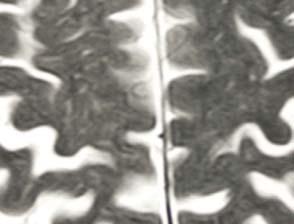

Brain activity comparison

See a healthy brain and a comatose brain side by side Brain in a coma

Healthy brain

This MRI scan shows the normal anatomy of the cerebral hemispheres. Two types of brain tissue are visible: grey matter which performs computations (the darker tissue) and white matter (lighter fi bres), which transmits signals between the various regions of this complex organ. This scan shows irreversible destruction of the white and grey matter of the brain’s frontal and cerebral regions (upper centre). Normally the white matter transmits the grey matter’s computations, but here the two are almost indistinguishable, making it impossible for the organ to communicate. Recovery depends on the cause of the coma. Infection-induced comas may reverse with antibiotics, while excess pressure may resolve by draining fl uid. Comas rarely last more than two to four weeks, but recovery is gradual. Patients may be alert for only a few minutes, progressing to longer periods. Their outcome relates to their Glasgow Coma Scale result – those who scored lowest in the fi rst 24 hours will likely die or remain in a vegetative state, while those who score at the higher end may make a full recovery. Coma survival rates are around 50 per cent. After a coma the patient may only recall memories after coming to and will usually wake in a profound state of confusion, not knowing how they got there. However, they tend to regain brain function gradually, often with the help of physiotherapy and occupational therapy to relearn basic skills like walking, talking and eating.